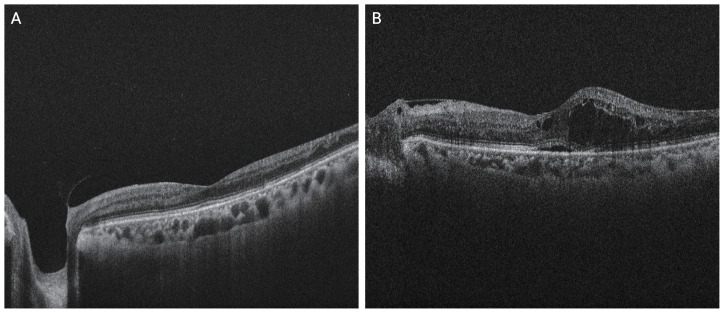

Methods: The medical records of 40 patients (45 eyes) diagnosed with diabetic NVG, between January 2017 and April 2022, were retrospectively reviewed. At the time of NVG diagnosis, central retinal thickness (CRT) was measured using optical coherence tomography. The eyes were categorized into groups with ME (CRT ≥300 μm) and without ME. Systemic diseases, ocular parameters, and prior treatments such as panretinal photocoagulation and intravitreal anti-vascular endothelial growth factor injections were compared between the two groups.

Results: Only 6 of the 45 eyes (13.3%) had ME at the time of NVG diagnosis. No significant differences were observed between the ME and non-ME groups in terms of systemic diseases, including hypertension, hyperlipidemia, ischemic heart disease, cerebrovascular accident, and chronic kidney disease. Other clinical characteristics, such as age, sex, body mass index, smoking history, best-corrected visual acuity, intraocular pressure, lens status, and history of ocular treatment, were also comparable between groups.